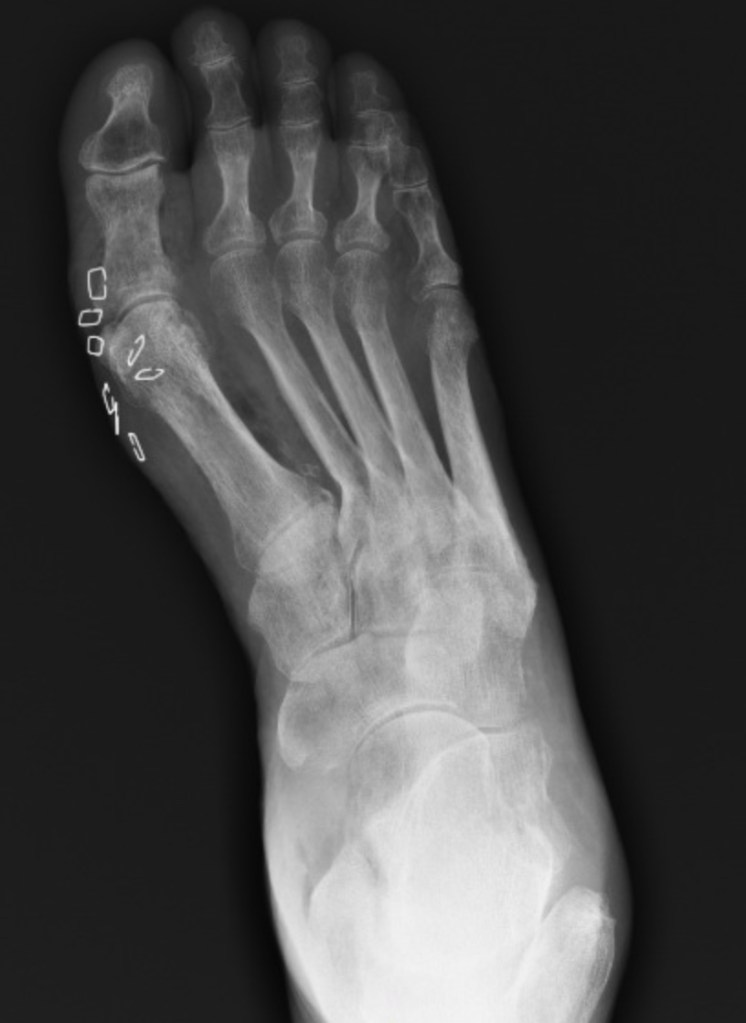

What’s the diagnosis? By Dr. Patrice Baptista @emdaily.cooperhealth.org